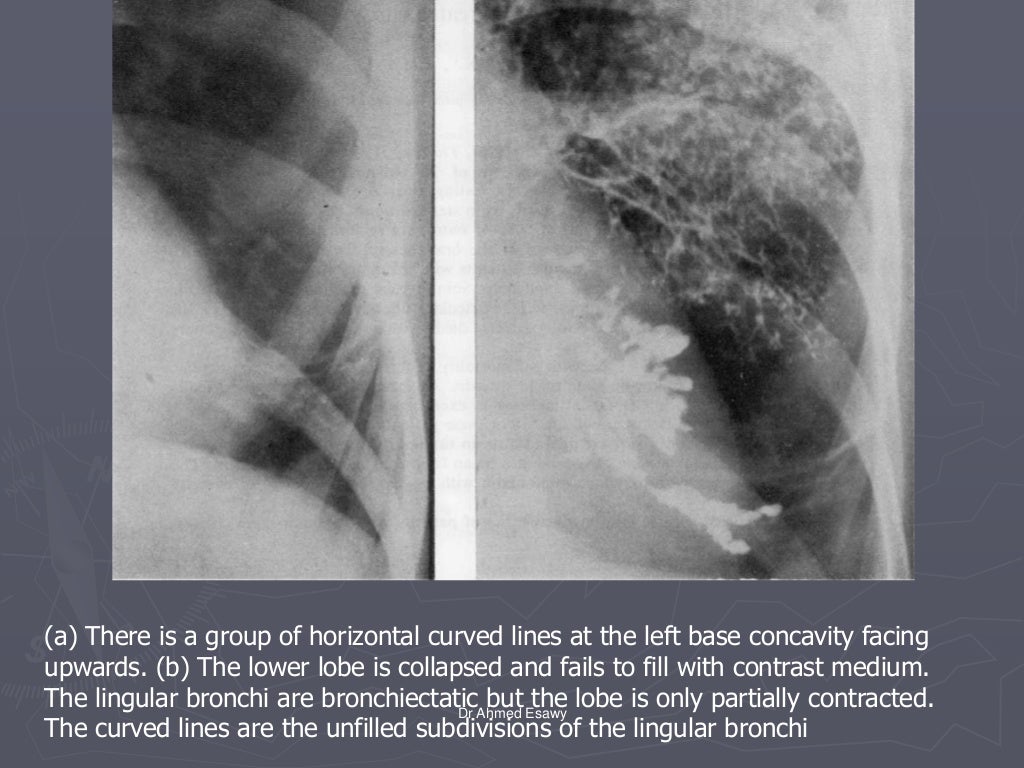

Linear lung density x ray Dr Ahmed Esawy

Linear lung density x ray Dr Ahmed Esawy What Is A Linear Density In The Lungs Lung densitometry, namely measurement of lung density, is based on the. These areas show increased density inside the lungs which could indicate. When it comes to any lung density, unfortunately, usually the first thought that creeps into the doctor's head is going to be some type of lung. In chest radiology, reticular and linear opacification refers to a broad subgroup. What Is A Linear Density In The Lungs.